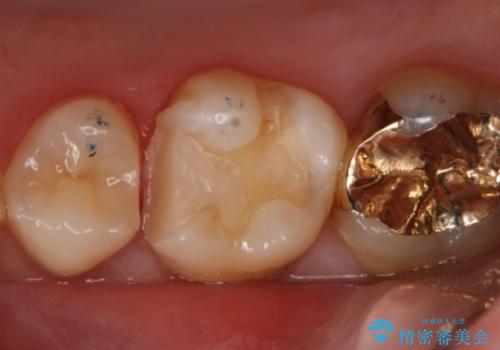

- 右上6番の銀歯のやりかえを希望し来院された患者様です。

切削量や形状からインレーでの治療を計画しました。

ご本人が金歯を希望されたため、ゴールドインレーでの治療を選択しました。